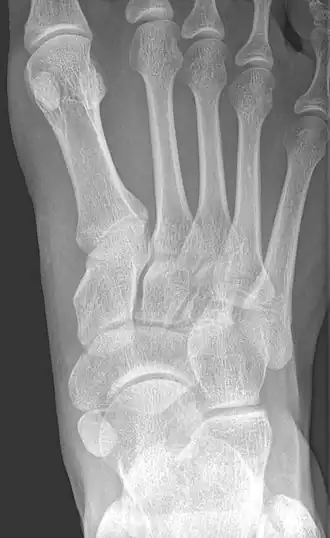

Accessory navicular bone

An accessory navicular bone is an accessory bone of the foot that occasionally develops abnormally in front of the ankle towards the inside of the foot. This bone may be present in approximately 2-14% of the general population and is usually asymptomatic.[1][2][3] When it is symptomatic, surgery may be necessary.

The Geist classification divides the accessory navicular bones into three types.[3]

- Type 1: An os tibiale externum is a 2–3 mm sesamoid bone in the distal posterior tibialis tendon. Usually asymptomatic.

- Type 2: Triangular or heart-shaped ossicle measuring up to 12 mm, which represents a secondary ossification center connected to the navicular tuberosity by a 1–2 mm layer of fibrocartilage or hyaline cartilage. Portions of the posterior tibialis tendon sometimes insert onto the accessory ossicle, which can cause dysfunction, and therefore, symptoms.

- Type 3: A cornuate navicular bone represents an enlarged navicular tuberosity, which may represent a fused Type 2 accessory bone. Occasionally symptomatic due to bunion formation.